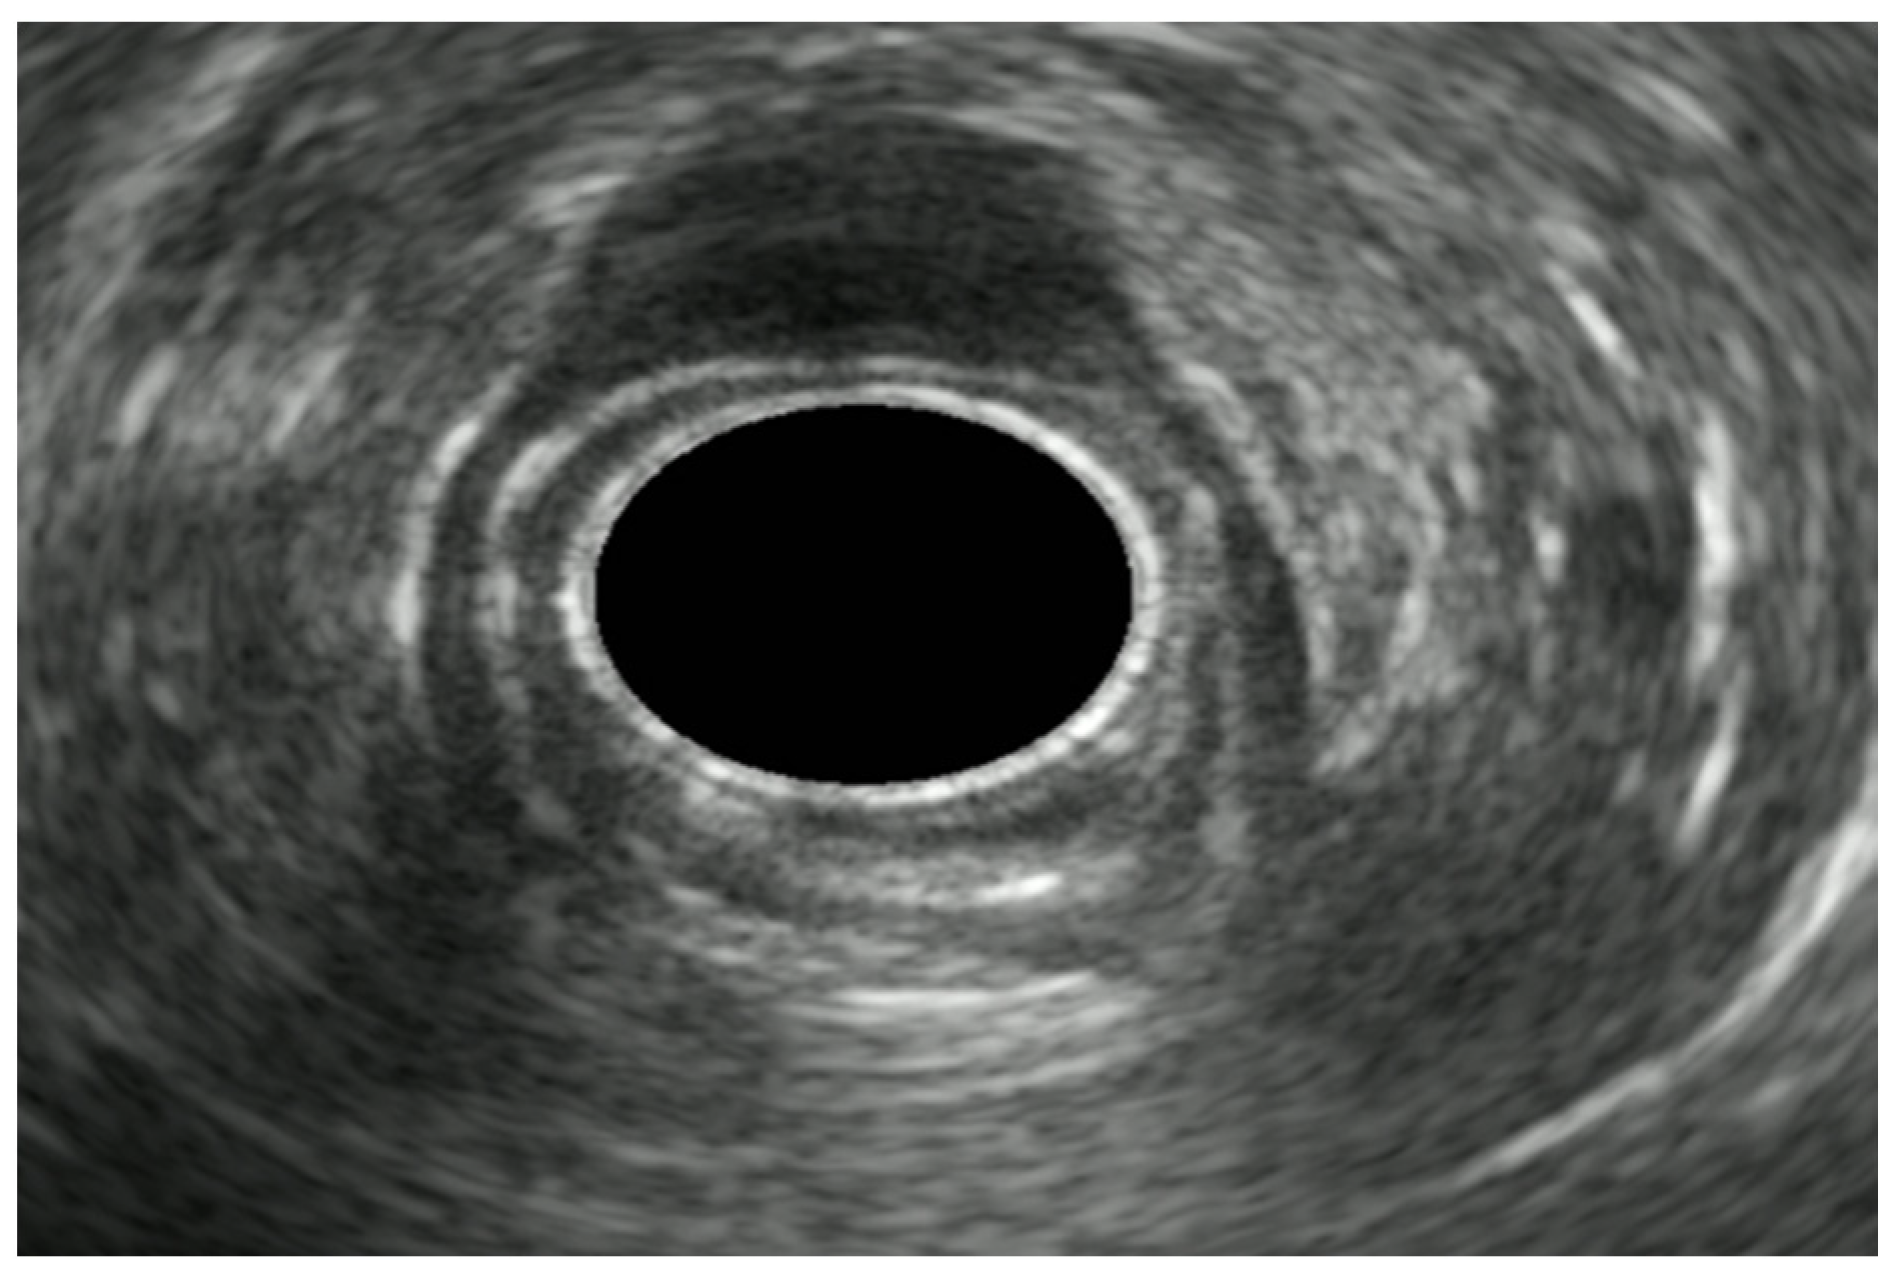

7. Endoscopic Rectal Ultrasound

8. Rectal Neoplastic Lesions

8.1. Rectal Superficial Cancer

8.2. Advanced Rectal Cancer